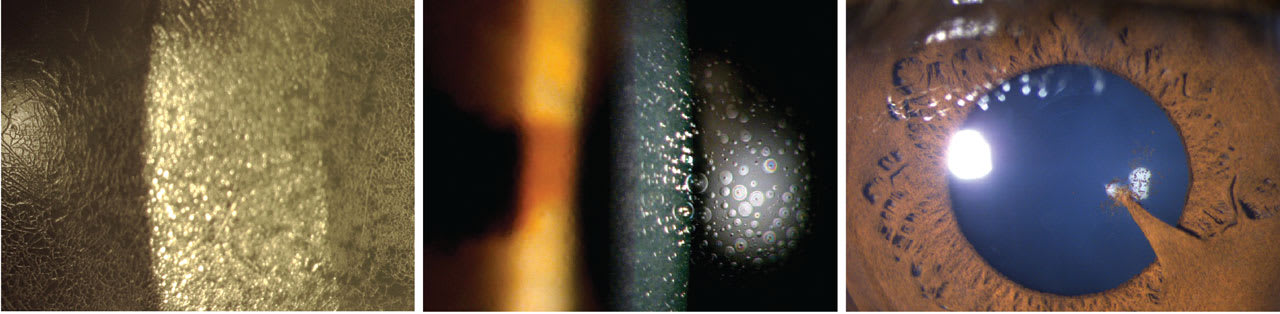

Photo Contest Winners

Almost 50 photos were submitted for the annual GSLS Photo Contest. The winning photos appeared on the cover of the April 2024 issue of Contact Lens Spectrum. The winners (pictured left to right) are:

First Place: "Charlotte’s Web, Scleral Lens Edition" by Karen Carrasquillo, OD, PhD

Second Place: "Psychedelic Tear" by Vicente Berbegal Garcia